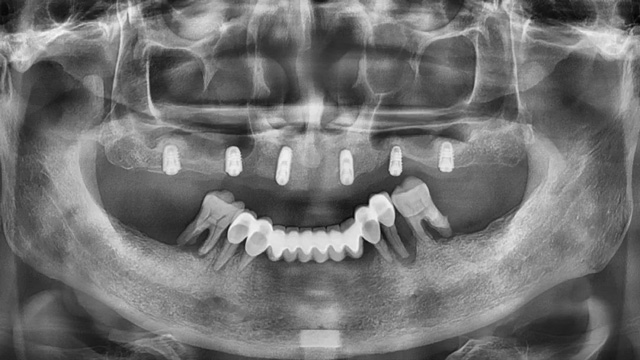

王先生全口種植后全景片(2024年4月/新橋口腔成都衣冠廟院區(qū))

2023年底,王先生終于決定去種牙,他就近選擇了金牛區(qū)的一家診所。按照醫(yī)生的方案,拔掉上面4顆門牙做了半口種植,共埋入了6顆種植體,手術(shù)后戴上了臨時(shí)活動(dòng)牙冠。按計(jì)劃,半年后就可以安裝正式牙冠了。

當(dāng)天的面診和檢查結(jié)果顯示,王先生在金牛區(qū)某口腔診所種植的6顆種植體中,有一顆出現(xiàn)松動(dòng),一顆種植體頸部暴露。

李陽軍醫(yī)生建議拔掉松動(dòng)的種植體,將暴露的種植體重新縫合后完全埋入牙槽骨,另外加種3顆以增強(qiáng)穩(wěn)定性。至于下半口,原來的烤瓷橋跨度太大,非常不規(guī)范,屬于不良修復(fù)體,醫(yī)生建議拆除并拔掉殘留的牙齒,做半口種植。

“他的下牙長期存在牙周問題和不良修復(fù)體,牙齒基本上都松動(dòng)了,為了增強(qiáng)穩(wěn)定性我給出的方案是種6顆而不是4顆。很幸運(yùn)他的骨量不算太差,通過少量植骨后進(jìn)順利埋入了6顆種植體。”

按此方案,王先生只接受了一次手術(shù),就完成了松動(dòng)的種植體拆除和拔牙、種牙、戴臨時(shí)牙冠等一系列的治療,一次解決了困擾多年的缺牙問題。